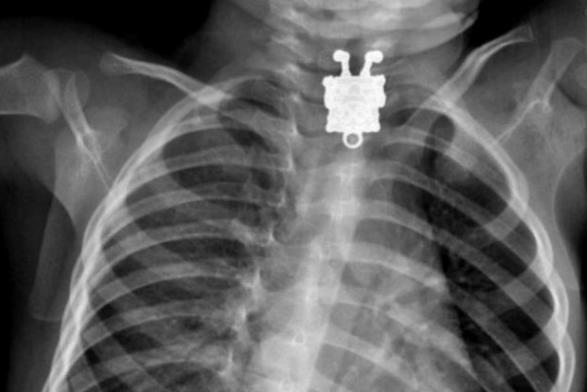

El dr. Ghofran Ageely, un radiólogo del hospital de la universidad de King Abdulaziz, en… Leer más »Bob Esponja fue encontrado en el cuello de un niño (Imagen)